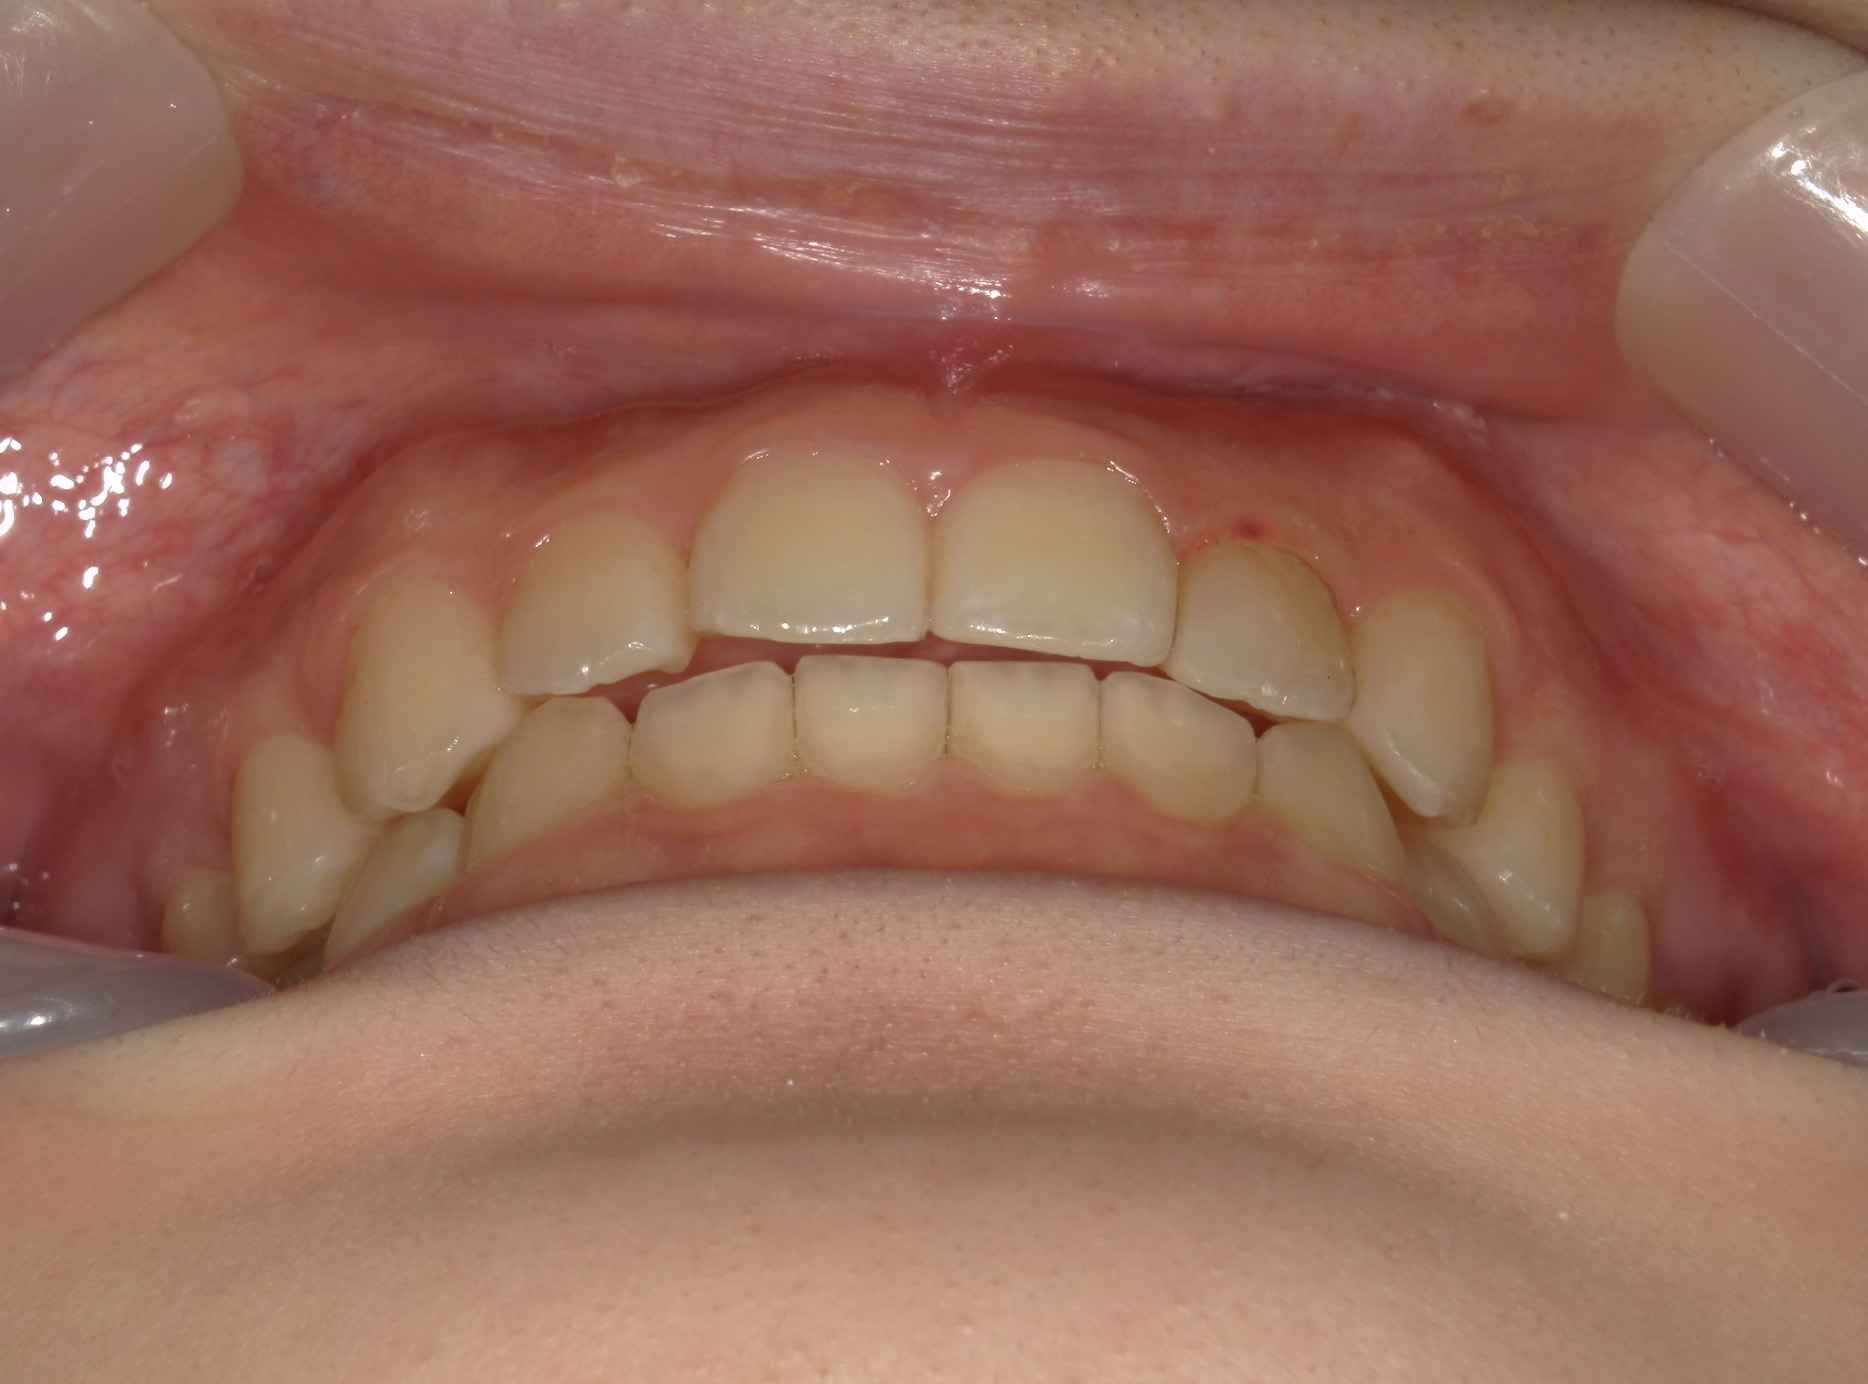

インビザライン矯正 症例(19)

主訴: 左上犬歯が出ているのが気になる

再設計3回

Ⅱ級ゴムを併用。

| 治療期間 | 4年5ヶ月 |